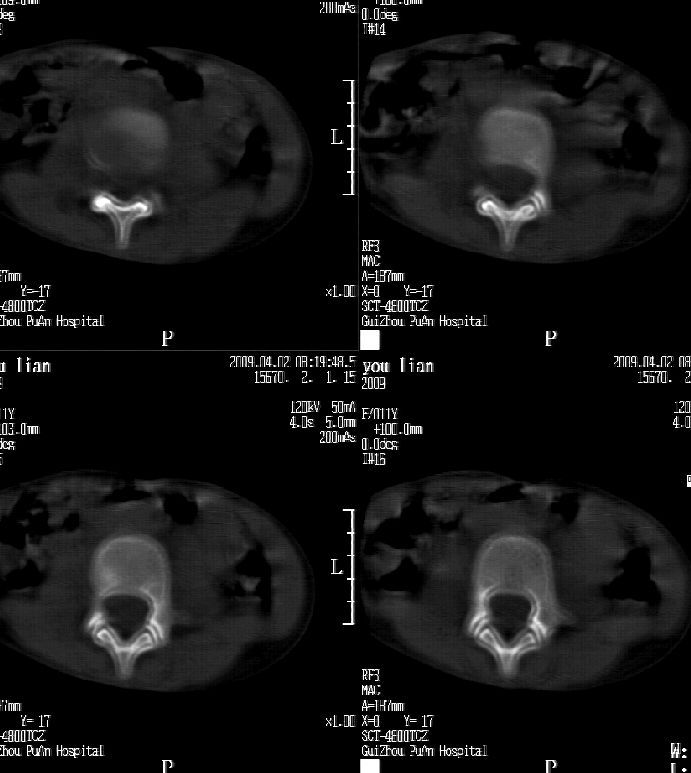

患儿女,11岁,因“腰痛,腰部活动受限10余天”入院。

10余天前,患儿无明诱因出现腰部疼痛,为持续性钝痛,以右侧为著,伴腰部活动受限,有发热,具体体温不详,无寒战、黄疸、盗汗、咳嗽,无尿频、尿急、肉眼血尿。

乍一看像是嗜酸性肉芽肿,但看到ct表现骨质破坏及软组织肿胀考虑结核可能性大,鉴别恶性肿瘤.

本例ct图像太不清楚了,而且不知道有没有传完,如果软组织病变只局限性于那几个层面的话多考虑嗜酸性肉芽肿,其次为其他肿瘤,结核椎旁软组织较广泛,在本例没有太典型表现,建议楼主(孩子父母吧)把所有的软组织窗图像(白色的那种)按顺序全部转上来.

考虑l3嗜酸性肉芽肿。